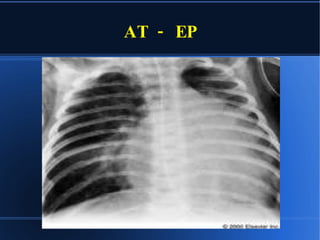

RX CON/SIN CARDIOMEGALIA OLIGOHEMIA CONGESTION CRECIMIENTO AD CRECIMIENTO VI AP CONCAVA

AT - EP